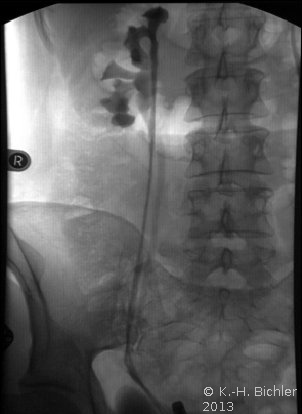

Das retrograde Pyelogramm rechts bestätigte die Diagnose. Es fanden sich zwei getrennte Ostien und in der retrograden Darstellung zwei Ureteren, wobei die distale Harnleiteröffnung zu der

oberen kleinen Niere gehörte

Weigert-Meyersche RegelDer Ureter des unteren Anteils mündet orthotop, der Ureter des oberen Anteils kreuzt den des unteren und mündet kaudal davon.

Unter Berücksichtigung der immer wieder aufgetretenen Harnwegsinfekte wurde die dysplastische kleine Niere entfernt (Abbildung 5)